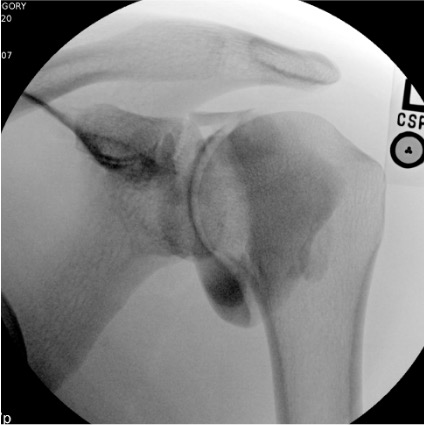

Shoulder

Needle placementPost-injection